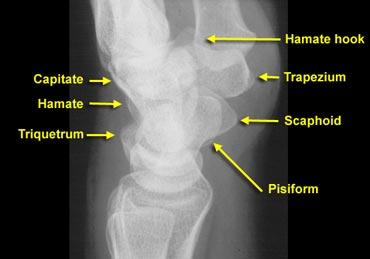

Chỉ trên hình nghiêng đúng tư thế mới có thể thấy riêng biệt và thẳng hàng các bờ gan tay của xương thuyền, xương đậu và xương đầu như minh họa bên trái.

Xương nguyệt là xương hình bán nguyệt khớp với đầu xa xương quay. Nhìn xuyên qua đó, có thể thấy mặt lồi của xương thuyền.

Phía xa xương thuyền là xương thang. Xương có hình góc cạnh nhìn thấy ở phía lưng là xương tháp.

Xương vuông bắc cầu giữa nửa gần và nửa xa của cổ tay là xương đậu.

Xương đầu là xương tròn khớp vào mặt xa của xương nguyệt.

Ở phía xa, giữa các xương đốt bàn tay, có thể nhận ra móc xương móc.